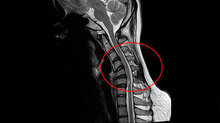

醫師提醒,低頭族若是發現脖子疼痛、手麻等症狀久久未癒,而且範圍有變大的現象,務必盡快就醫檢查。(圖/亞洲大學附屬醫院提供)

1名27歲從事視覺設計的年輕女子,因長時間低頭繪圖,去年開始感覺到肩頸痠痛,甚至偶爾會出現手部麻痺,「筆都拿不穩」,經轉診至醫院安排核磁共振,赫然發現竟是脊髓空洞症,雖然還未嚴重到必須開刀手術治療,但醫師仍建議後續必須定期追蹤,同時務必要減少低頭時間,以及維持正常姿態,以免症狀持續惡化。

針對病人的情況,亞洲大學附屬醫院副院長、神經外科主任林志隆說明,患者這6、7年來姿勢不當,頸椎長期承受壓力,經核磁共振檢查後,發現已經出現脊髓空洞症的前兆,脊髓內滲入不少液體,幸好發現得早,空洞的情況相當輕微,評估後無須開刀引流,但後續除了改正姿勢,也要定期追蹤觀察空洞的發展情狀。